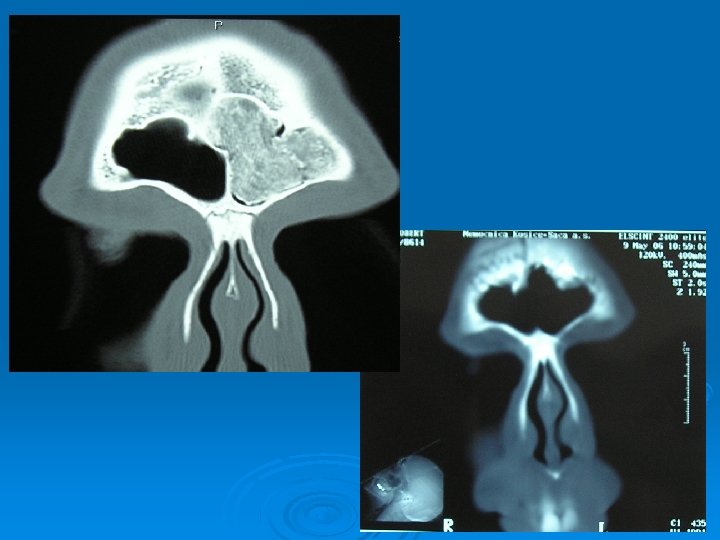

Kazuistika č. 3 – 68 ročná pacientka M. L. Subj: 3 -4 mesiace úporné bolesti hlavy, pocit tlaku v čele CT PND: 2 osteómy mediálnej časti ľavej čelovej dutiny, väčší 1, 5 cm takmer blokuje vývod Op. liečba: endoskopický prístup - Draf II vľavo Histológia: Osteoid osteoma

FESS prístup - Draf II